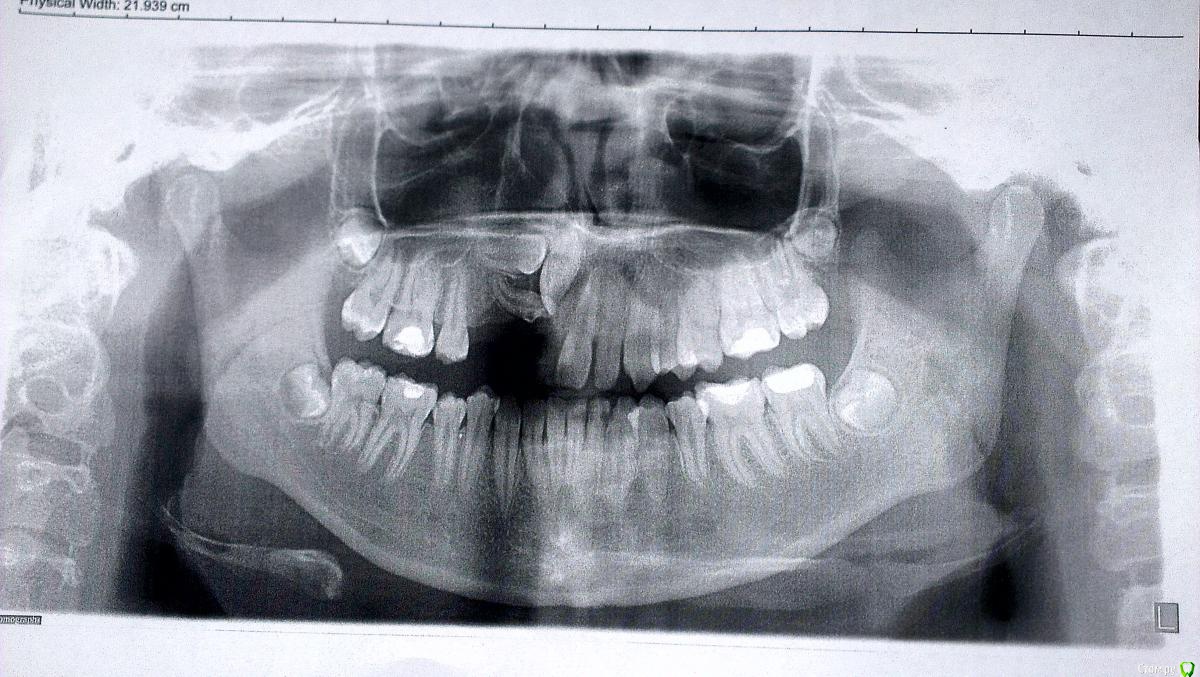

Солнечный СВЕТ Опубликовано 15 февраля, 2015 Поделиться Опубликовано 15 февраля, 2015 Девочка 14 лет, зубы не прорезались,у девочки уже комплекс,родители тоже не знают что делать,готовы ехать в другой город только бы помог кто нибудь,сейчас носит чсп,какие возможны варианты лечения и куда можно обратиться чтобы смогли помочь?!?!?!?! Ссылка на комментарий

SDC Опубликовано 15 февраля, 2015 Поделиться Опубликовано 15 февраля, 2015 (изменено) Ориентировочный план: 1-е посещение : консультация с КТ и слепками (принятие решения о том в какой последовательности вытягивать зубы) скорее всего, возможно по моделям и КТ без пациентки. 2-е посещение: начало лечения, будет начинаться с раскрытия и диагностического вытягивания ретинированных зубов (последовательность будет ясна после диагностики КТ). Аппарат для диагностического вытягивания: скорее всего кантилевер. В среднем плановые визиты на 1м этапе : 1-е с периодичностью в 1,5-2 месяца. После положительной динамики выдвижения ретинированных зубов, переход на полную брекет-систему. Изменено 15 февраля, 2015 пользователем SDC Ссылка на комментарий

Molox Опубликовано 28 февраля, 2015 Поделиться Опубликовано 28 февраля, 2015 Полностью согласен насчет кт, но оптимизма мало. По итогу можно получить неслабые карманы в области этих зубов, т.к. низкий уровень кости. Ссылка на комментарий

krokomot Опубликовано 28 февраля, 2015 Поделиться Опубликовано 28 февраля, 2015 (изменено) ничего подобно не произойдет если все делать правильно, но возможно, что головоломка и не сложится, хотя складывались и не такиеобязательно :наладить гигиену,сделать модели и ктфиксация системывытяжениеПорядок время и последовательность определяться после изучения кт и моделей. Изменено 28 февраля, 2015 пользователем krokomot 1 Ссылка на комментарий